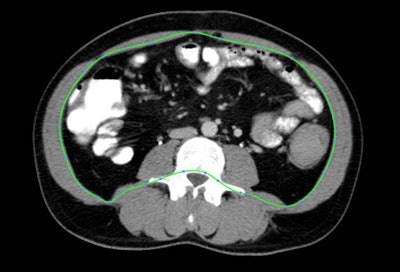

| Fatty regions were isolated and measured based on attenuation of CT images at a single slice (L4/5 intervertebral disk + 6 cm). All images courtesy of Áine Ní Laoire and lead investigator Dr. Michael Maher, University of Cork, Ireland. |

All fat measurements were taken at a single CT slice location (L4/5 intervertebral disk + 6 cm), with investigators measuring visceral adipose tissue area (VAT area, cm2) and subcutaneous adipose tissue area (SAT area, cm2) based on tissue attenuation ranging from -150 to -50 HU. Body mass index was calculated from measurements taken at the L1 level, and CT images were examined using an open-source software package (OsiriX, Geneva), Laoire said. Fifty images were randomly selected for reliability testing using the Bland-Altman method and were found to be acceptable.